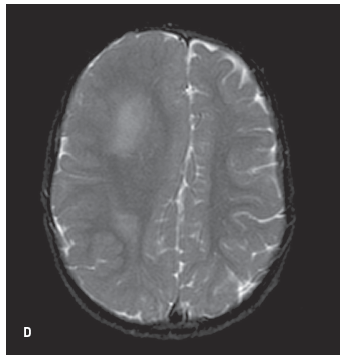

An MRI scan of the brain revealed a marked asymmetry in the size of the cerebral hemispheres with a larger hemisphere present on the right (A, B, and C). Also noted was nonlissencephalic cortical dysplasia involving the right frontal, parietal, and temporal lobes with several foci of heterotopic gray matter. The right subcortical white matter demonstrated abnormal hyperintensities (D). These findings were consistent with a diagnosis of right hemimegalencephaly.

Hemimegalencephaly is a rare congenital defect of neuronal migration and proliferation. The defect is characterized by hypertrophy of all or most of one hemisphere. Children typically present with seizures, cranial asymmetry, or hemiparesis.

MRI is considered the best tool in diagnosing hemimegalencephaly. Excessive growth of neurons and astrocytes manifests into a thickened cortex. There is a flattened inner cortical border and fused microgyri with a smooth cortical surface.5